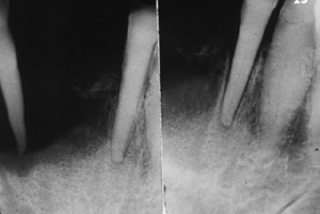

Reabsorción ósea Una radiografía de este

paciente de 62 años de edad descubrió una reabsorción ósea que no es

típica de la enfermedad periodontal. Esto debe alertar de una

enfermedad seria y debe indicarse la biopsia. Desgraciadamente, en

este caso el odontólogo realizo las exodoncias y al ver que las heridas

no cicatrizaban, decide realizar la interconsulta al especialista. |